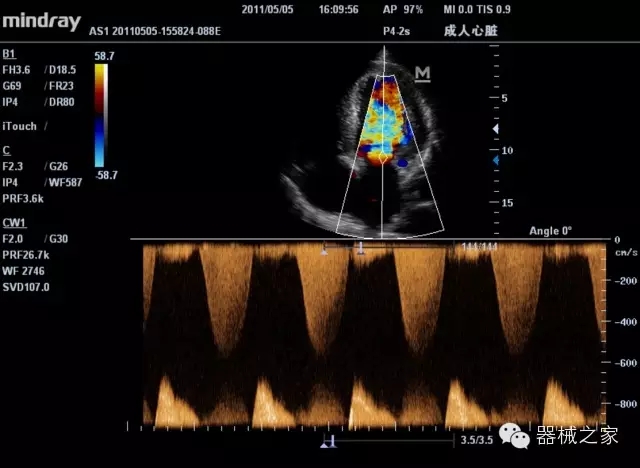

臨床圖片賞析

產(chǎn)品特點

8倍波束并行處理系統(tǒng)

·在便攜式緊湊平臺上采用更多倍波束并行接收信號處理模式,無論二維還是彩色血流圖像狀態(tài)下,擁有更靈敏的回波頻移捕獲能力,大大提高時間分辨率,尤其使得心血管表現(xiàn)更為突出;